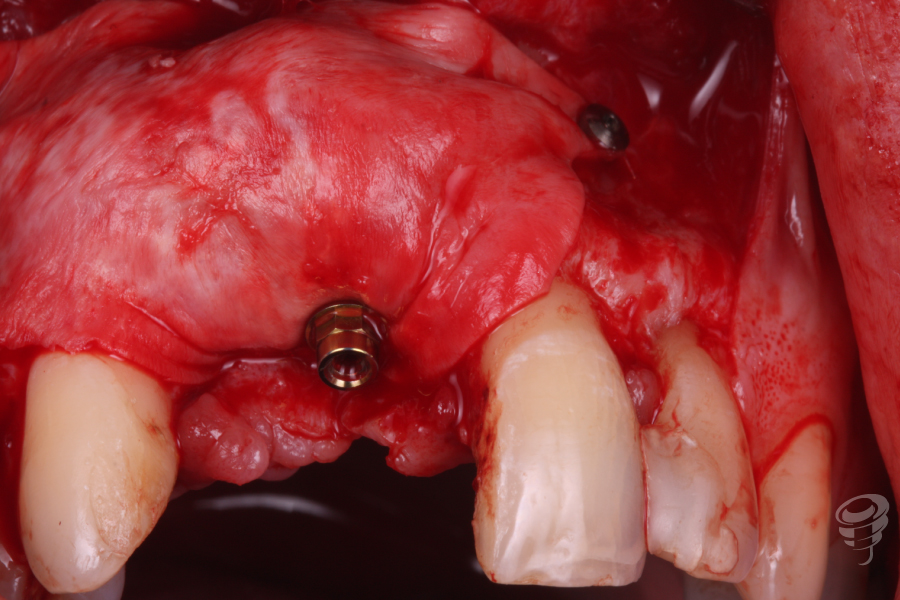

Colocamos un tornillo de Tent Pole en la zona del defecto creado por el implante en 12 para conseguir un relleno óseo adecuado.

Imagen 5

Imagen 6

Una vez estabilizado el tornillo Tent Pole, manteniendo la distancia al hueso remanente, procedemos a rellenar con hueso autólogo de fresado y xenoinjerto. Posteriormente colocamos una membrana de colágeno fijada con chinchetas. (Imagen 7 y 8). Finalmente procedemos a realizar la sutura.